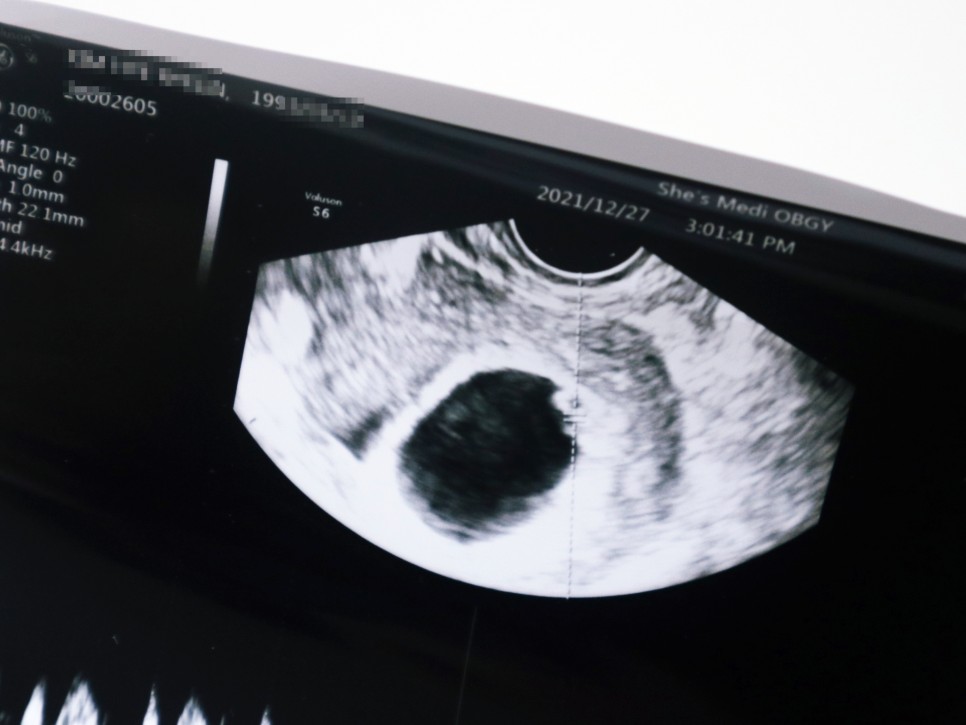

임신 7주 0일 (21년 12월 27일) 임신 7주차 태아심박동수 태아소견 신장 0.9cm

임신 4주 5일 첫 방문 때 0.2cm 짜리 아기 집을 봤는데 실제로 태아는 그걸 몰랐던 거예요.그래서 이날은 아기 집에 두 대를 확인하고 심박수를 체크하는 날이었어요.임신 7 주째, 초음파 상 아기 집도 엄청 커지고 있었는데, 그 속에서 젤리 곰의 아기를 발견할 수 있었습니다. 노른자도 꼭 확인했어요선생님이 보시기에 넓은곳이 많은데 저위에 붙어있대 ㅋㅋㅋ

임신 초기에 엽산과 비타민D를 자주 먹으라고 소량의 피눈물은 괜찮지만 생리혈처럼 쏟아지는 증상이 있으면 바로 내원하라고 했습니다.아기 심장박동기도 굿!!!